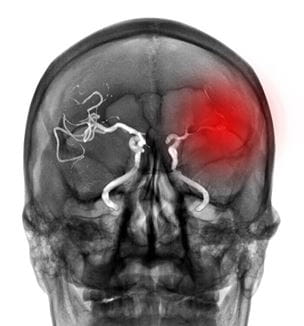

International Review Raises Concerns Over Studies of Intracranial Aneurysm Treatment